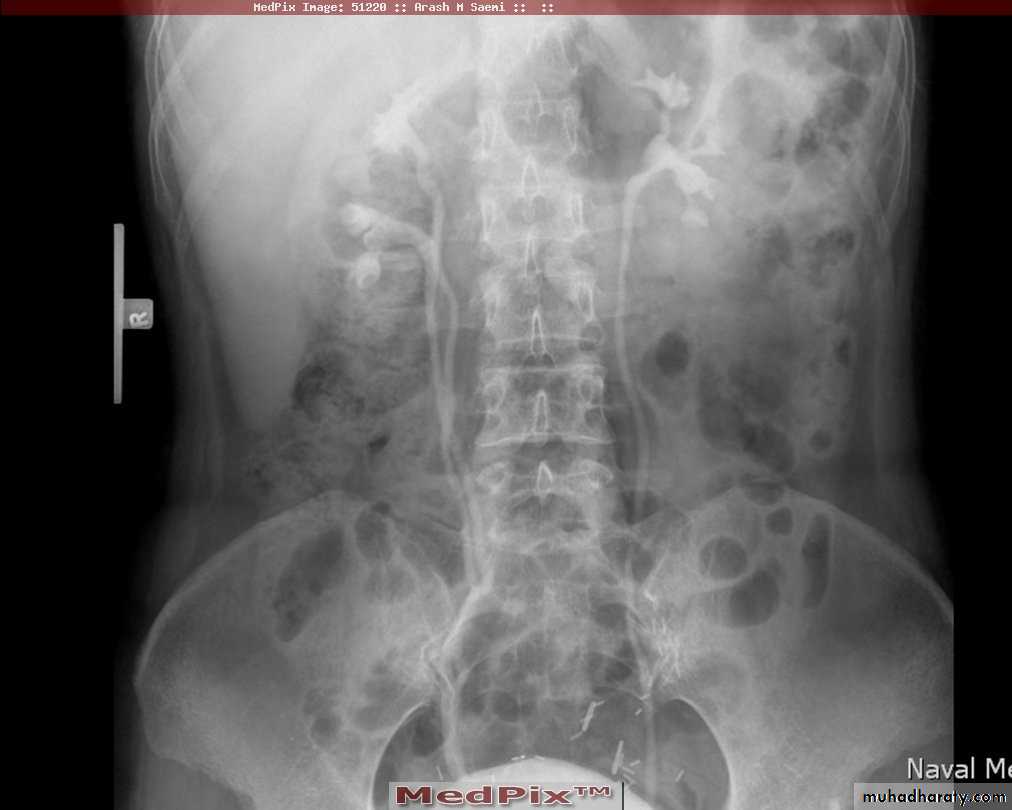

Poly cystic disease

Adult typePresent after the third decade of life , Familial.

Renal parenchyma is replaced by numerous cysts containing fluid , The cysts are of variable size ,

Clinically renal colic, loin mass , heamaturia and hypertension, Renal tissue interposed between the cysts after time dssimcted ended with renal failure

Almost bilateral.

IVU

Large kidney .

Lobulated out-line.

Distortion of pelvi- calyceal system depend on cyst size, number and position.

In advanced cases there is elongation and stretching of minor and major calyces ( spider leg).

In advanced cases IVU shows non-functioning kidney .